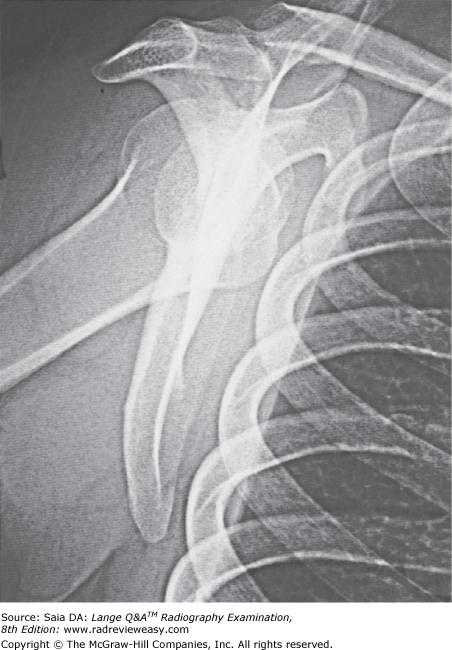

Which of the following statements is (are) true with respect to the radiograph shown in the Figure below?

- The acromion process is seen partially superimposed on the third rib.

- This projection is performed to evaluate the scapula.

- This projection is performed to evaluate the acromioclavicular articulation.

2 only